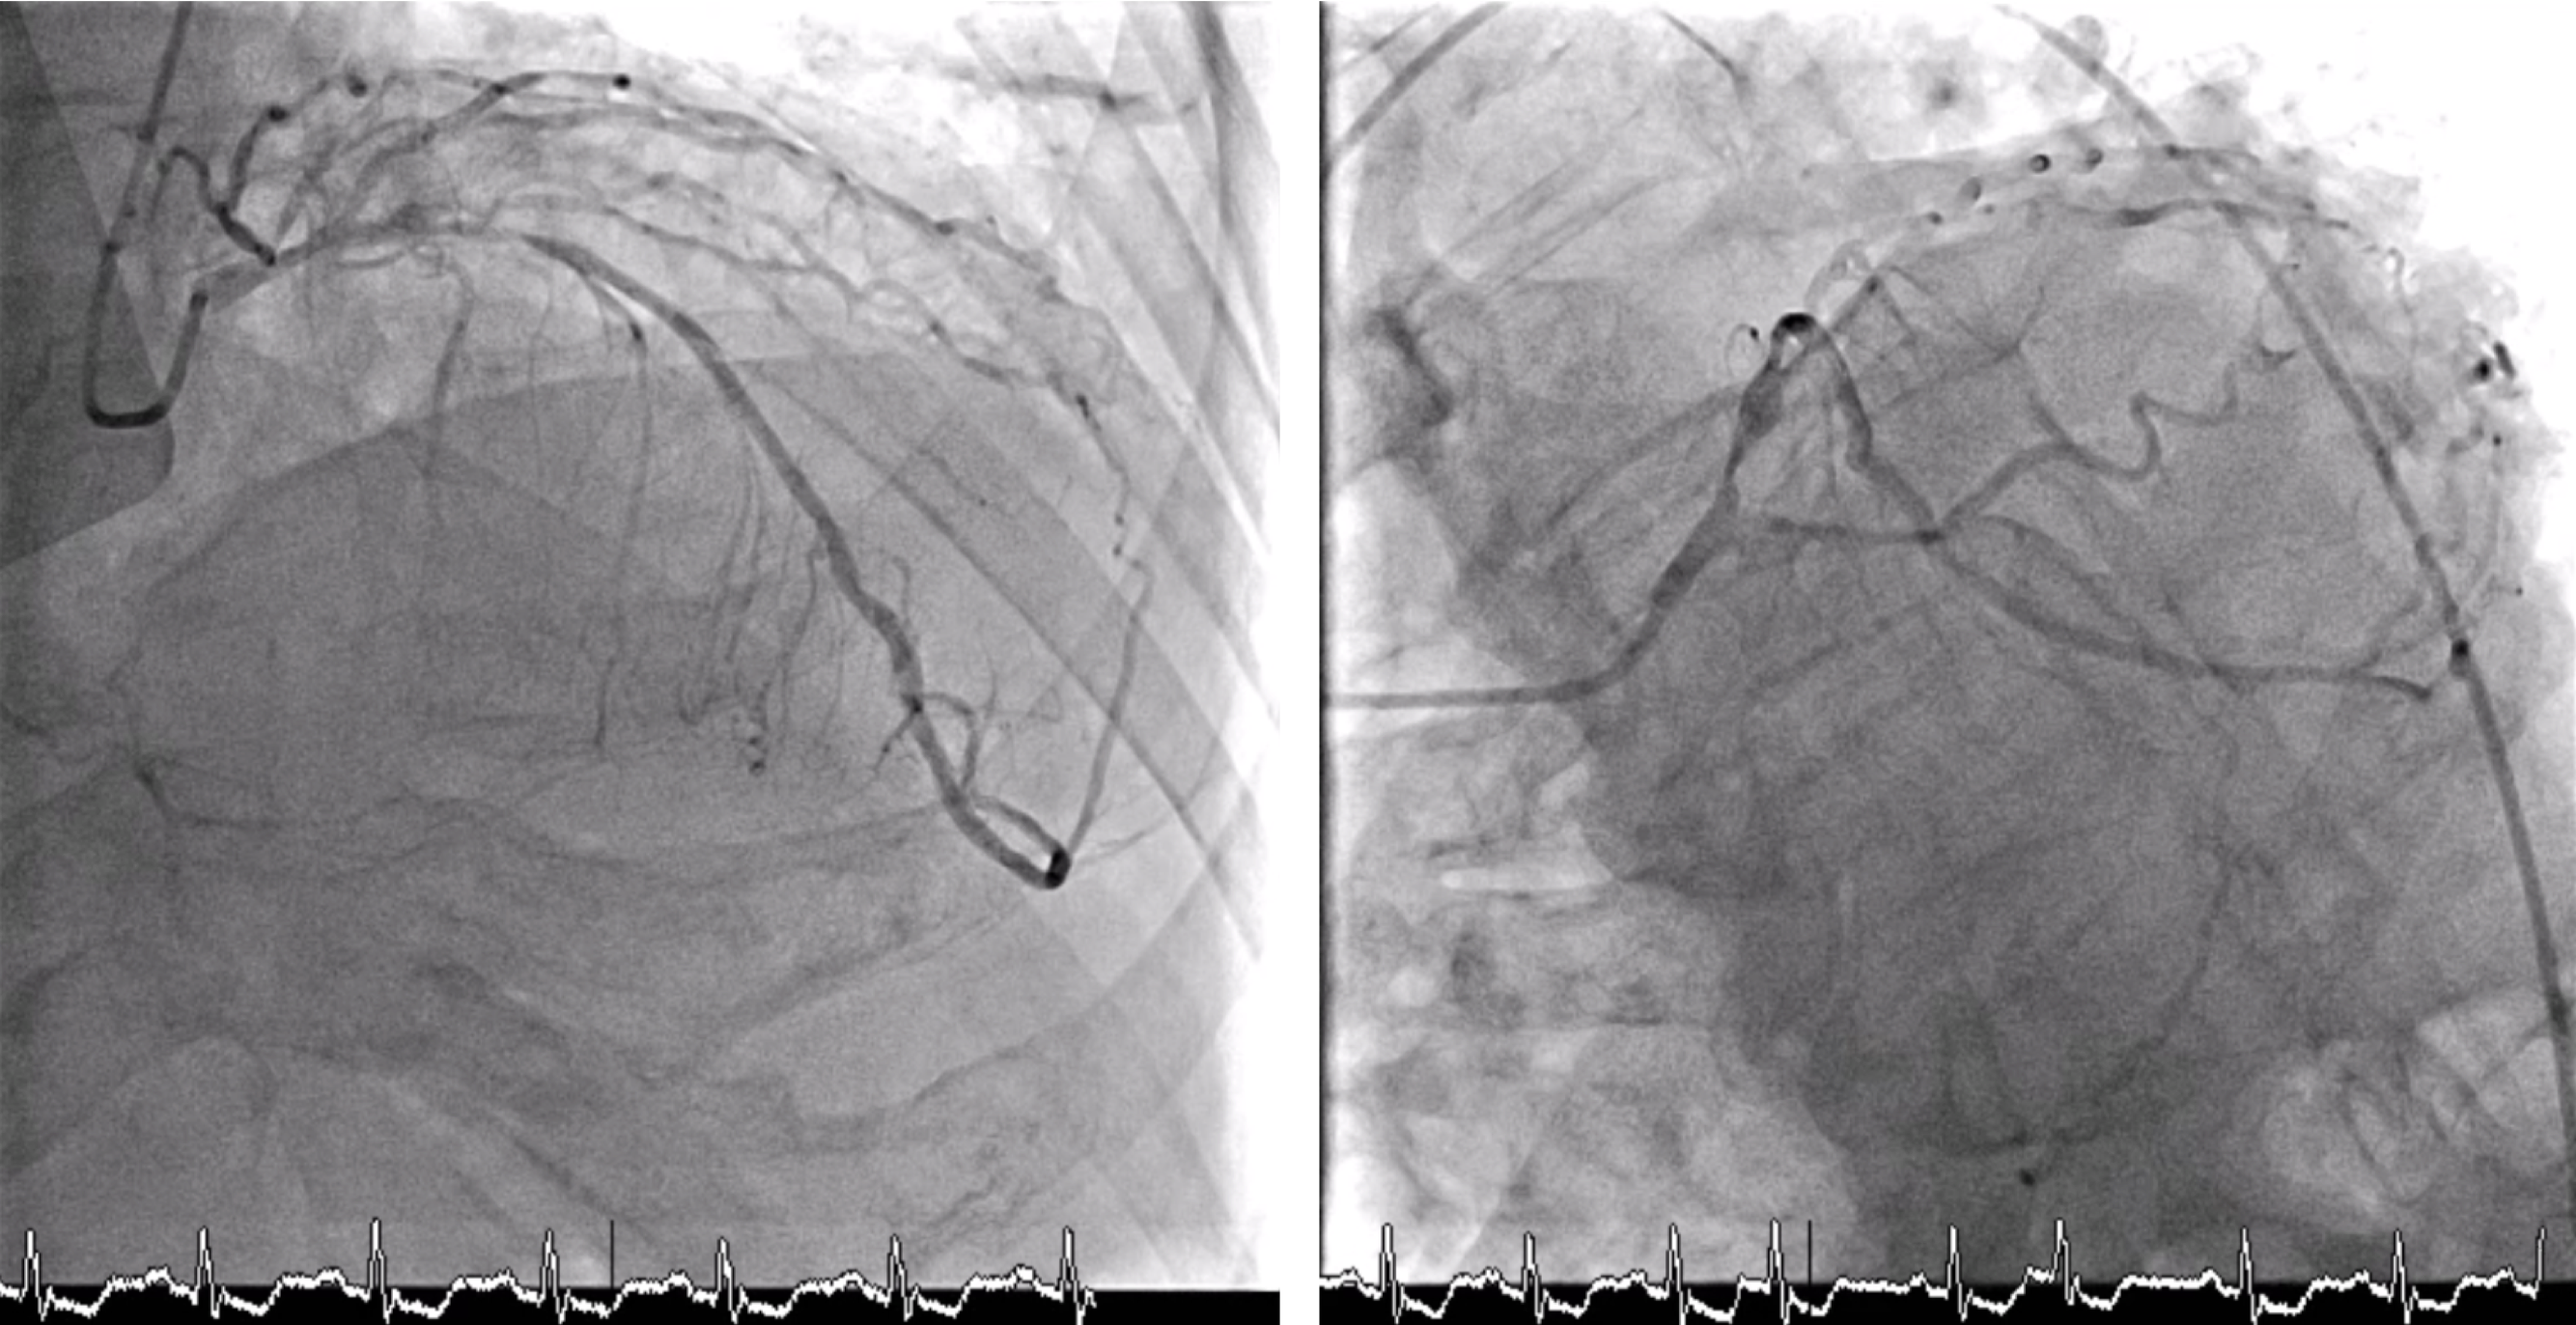

Relevant Catheterization Findings

- LM: Bifurcation lesion (medina 0, 1, 1) - LAD: Ostial stenosis 80 %, proximal stenosis 90%, middle stenosis 70 %, with collateral to LCx and RCA - LCx: Ostial stenosis 80 %, proximal stenosis 70 %, distal CTO, with collateral to RCA - RCA: Proximal stenosis 50 %, middle CTO, with intracoronary collateral - Syntax score: 37.5 - Right SFA: arterial sheath in situ with an iatrogenic AV fistula